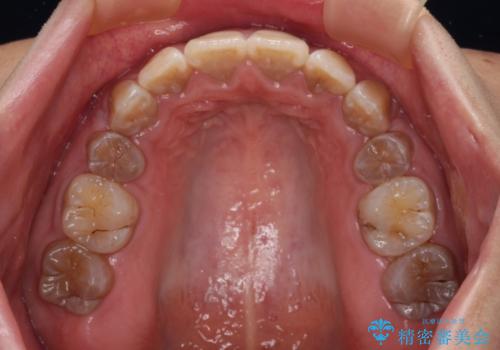

4本の歯を抜歯したことで、飛び出していた口元が引っ込み、横顔が大きく改善されました。

- 口元の突出感を気にして来院された患者様です。

上下前歯が著しく前突している状態であったので、上下左右の第1小臼歯4本を抜歯し、ワイヤー装置にて矯正治療を行うこととしました。